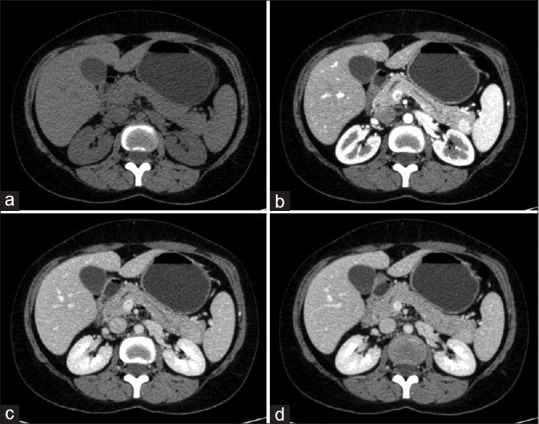

摘要:胰腺内副脾(IPAS)是一种罕见的由胚胎期脾芽未能融合引起的疾病。IPAS约占人口的1.1%至3.4%,诊断上存在重大挑战,常与胰腺肿瘤如胰腺神经内分泌肿瘤相似。我们报告两个IPAS病例,每个病例都说明了不同的诊断方法和结果。这些病例强调了考虑IPAS在胰尾高血管病变鉴别诊断中的重要性。先进的成像技术,如磁共振成像、计算机断层扫描、锝-99m显像和内窥镜超声引导下的细针穿刺,是区分IPAS与恶性疾病的关键,有可能防止不必要的手术干预。建议综合诊断方案,结合多种模式,以提高诊断的准确性和优化患者的结果。

Abstract: Intrapancreatic accessory spleen (IPAS) is a rare condition resulting from the failure of embryological splenic buds to fuse. Found in approximately 1.1% to 3.4% of the population, IPAS can present significant diagnostic challenges, often mimicking pancreatic tumours such as pancreatic neuroendocrine tumours. We report two cases of IPAS, each illustrating different diagnostic approaches and outcomes. These cases highlight the importance of considering IPAS in differential diagnoses for hypervascular pancreatic tail lesions. Advanced imaging techniques such as magnetic resonance imaging, computerised tomography, technetium-99m scintigraphy and endoscopic ultrasound-guided fine-needle aspiration are critical in distinguishing IPAS from malignant conditions, potentially preventing unwarranted surgical interventions. Comprehensive diagnostic protocols combining multiple modalities are recommended to enhance diagnostic accuracy and optimise patient outcomes.